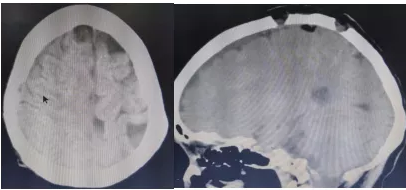

术前CT影像(肿瘤压迫脑组织、侵犯硬膜)

患者入院后予以充分的术前检查及准备、科内讨论后,认为右顶叶脑膜瘤诊断明确,治疗上可行手术切除。与患者家属充分沟通后,术前通过CT精确定位,于2021年11月01日在与麻醉手术科的通力合作下,完整切除颅内肿瘤及其所累及的脑膜组织。手术过程顺利,术后第二天患者就可下床活动,后经进一步的中西医结合康复治疗,患者头痛,头昏等症状缓解,痊愈出院。

术后CT影像(肿瘤已经切除,脑组织压迫解除)

顶叶脑膜瘤因毗邻大脑感觉及运动功能区,且此处有较粗大回流静脉,一旦处理不当,极容易引起大出血及加重肢体功能障碍。我院神经外科经过努力,成功切除这例顶叶脑膜瘤,而且住院时间短、花费少、手术效果好,获得了了患者及家属的认可。